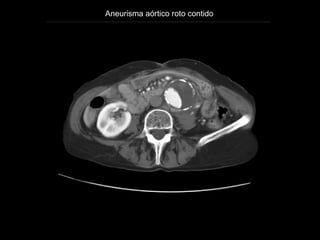

Aneurisma aórtico roto contido

http://emedicine.medscape.com/article/416397-overview